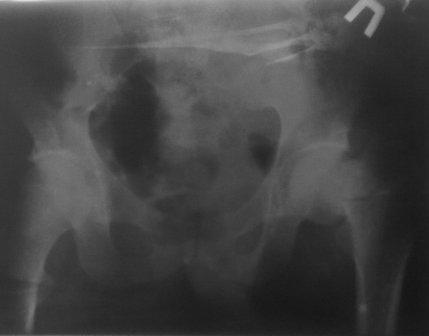

Больной 1980г.р. после тяжелой сочетанной травмы от 03.12.10г:

спленэктомии, ушивание разрыва печени, мн.переломы ребер. 05.02.11г

операция по поводу спаечной к/непроходимости.  И чрезвертельный

перелом правого бедра, посмотрел под скопией сращения нет, при

проверке двигается только дистальный отломок, а головка как бы

припаяна к вертлуге. Укорочение ноги 5см, нога ротирована вовнутрь и

приведена, из-за боли проверить обьем движения не удается.

В плане PFN -ChM , но может быть контрактура т/б сустава, или делать

открытым   способом (тогда большая кровопотеря, и так он

ослабленный), м/б предварительно аппарат таз-бедро или вытяжение

большим грузом.?